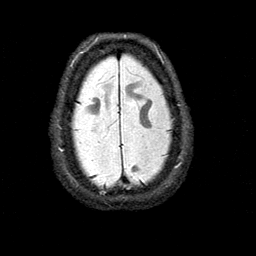

Alzheimer's disease MR T2-weighted -- Slice #42

[Home][Help][Clinical][Tour 1][Tour 2] Slice 42